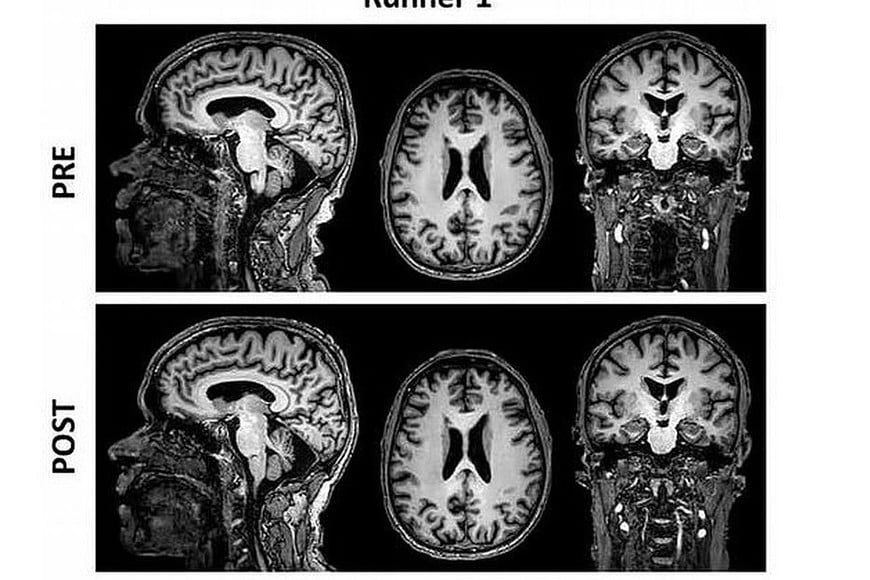

Resonancias magnéticas del corredor 1.

Para probar si ocurre lo mismo en humanos, los investigadores hicieron resonancias magnéticas a diez corredores de maratón (ocho hombres y dos mujeres) antes y 48 horas después de que hicieran una carrera de 42 kilómetros.

La reducción de mielina afectó a 12 zonas de materia blanca del cerebro relacionadas con la coordinación motora y la integración sensorial y emocional.